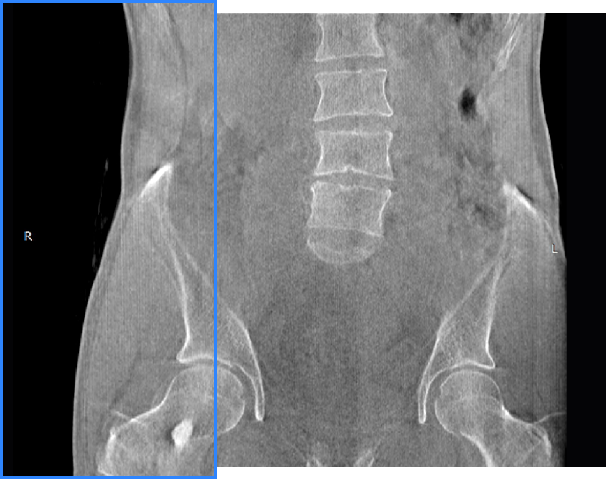

髖關節

腰椎